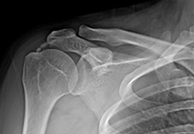

수술 중 제거 모습

석회성건염 수술 후